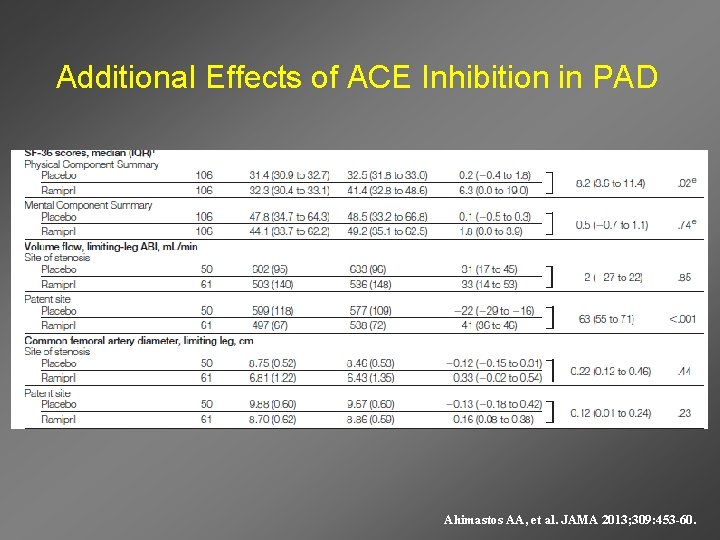

Effects of ACE inhibition on Claudication Ahimastos AA, et al. JAMA 2013; 309: 453 -60.

Additional Effects of ACE Inhibition in PAD Ahimastos AA, et al. JAMA 2013; 309: 453 -60.